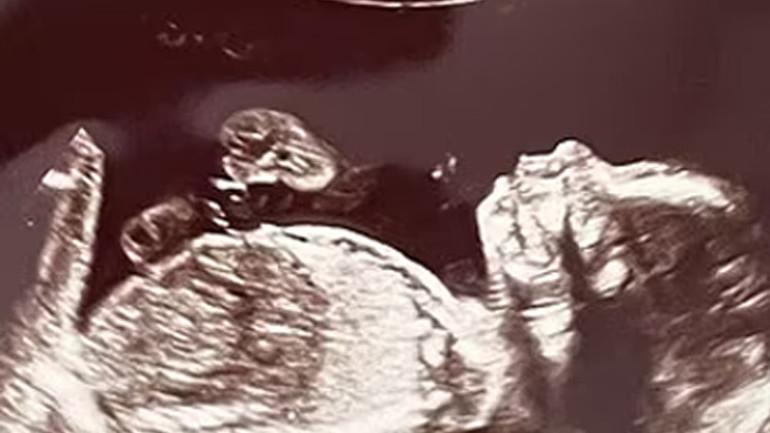

Daha önceki ilişkisinden de bir kızı olan anne adayı karnındaki dört bebeğin dördüz değil iki ayrı tek yumurta ikizi olduğunu öğrendi.

Bu keşfin ultrason teknisyenini bile şoke ettiğini anlatan anne adayı, "Taramayı ilk başlattığı zaman ekrana baktı ve 'A,B' yazdı. Durup bir an ona baktım. Görünen o ki ikizlerim olacaktı." diye sözlerine başladı ve şöyle devam etti;

"Teknisyenin kafasının karıştığını görebiliyordum. Ekranda gördüğü şeyin gerçek olup olmadığını anlamak için odadan çıkmak zorunda kaldı. Döndüğünde ise bana inanılmaz durumu anlattı. Dört bebeğe hamileydim. İki kız ve iki erkek."